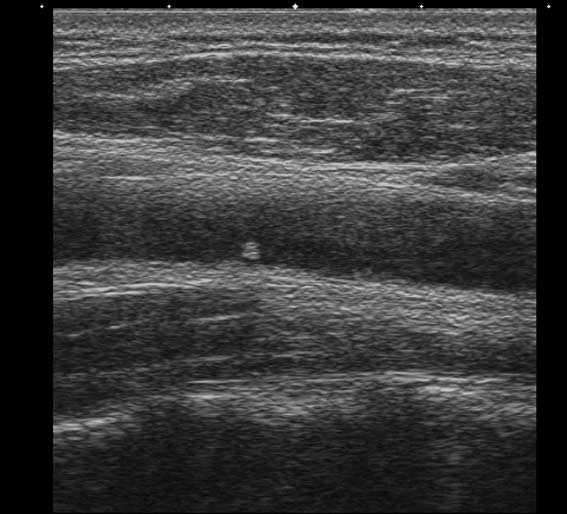

мужчина, 49 лет, при обследовании БЦА в общей сонной артерии визуализируется округлое образование 1.7х2.0 мм

Кальцинированная атеросклеротическая бляшка. Для уточнения ее истинного размера примените энергетический доплер.

локальная атеросклеротическая бяшка, которая не вызовет гемодинамически значимых изменений(если оценивать бляшку только в продольном сечении)